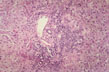

Piecemeal necrosis

Fig 59 - PIECEMEAL NECROSIS: In a patient with chronic active hepatitis B. Notice the disruption of the limiting periportal plate by dense mononuclear cell infiltrate which surrounds hepatocytes (peripolesis).